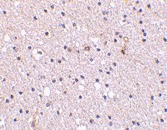

Supportive validation

- Submitted by

- OriGene (provider)

- Main image

- Experimental details

- Immunohistochemistry of Nicastrin in human brain tissue with Nicastrin antibody at 2.5 ug/ml.

- Validation comment

- IHC